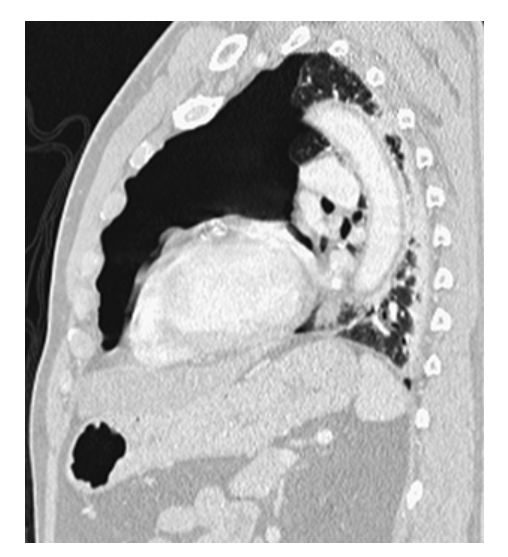

Pneumothorax. CECT sagittal MPR of the same patient shows a large left anterior pneumothorax.